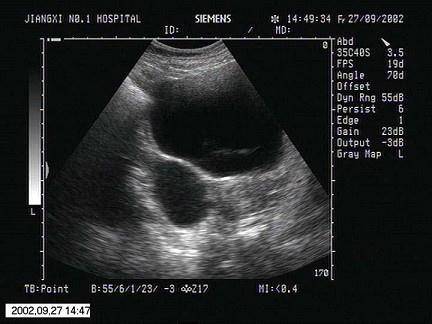

问题 女性,25岁,停经43天,尿妊娠试验阳性。结合超声图像,最可能的诊断为?(?)

选项 A.黄体囊肿 B.囊腺瘤 C.附件炎性包块 D.黄素囊肿 E.巧克力囊肿

答案 A